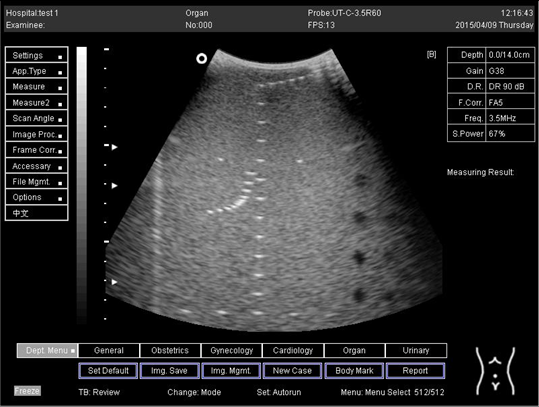

Table A5. The image taken for focal zone determination in different depth for curve probe.

Depth (cm)Diagram

14.0Biomimetics 07 00130 i031

16.0Biomimetics 07 00130 i032

18.0Biomimetics 07 00130 i033

24.0Biomimetics 07 00130 i034